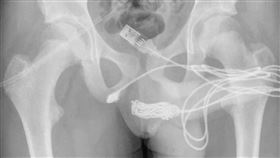

男塞USB線入私處!崩潰血尿拔不出

英國一名15歲的少年因為想知道自己的陰莖到底有多長,...